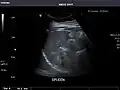

Spleen: Normal in size.

Spleen -